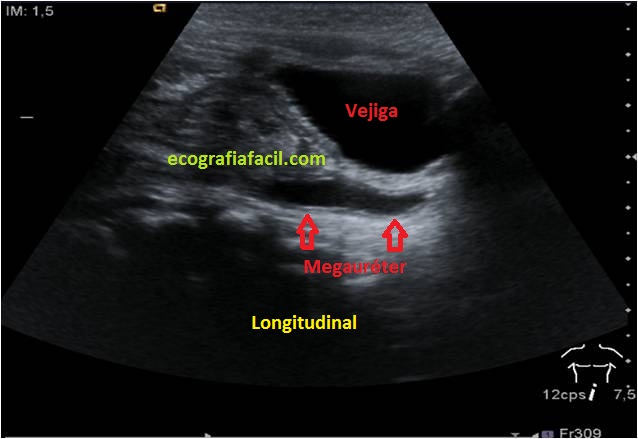

En Longitudinal, el Uréter derecho se alarga y busca su entrada en la vejiga, durante la exploración éstos pueden variar su tamaño al drenar la orina en la vejiga que puede estudiarse con Jet Ureteral que no es más que colocar el Doppler Color a la altura de la entrada de ambos uréteres en la vejiga y esperar a que la orina eyectada en la vejiga sea detectada por el Color como un flujo que nos representará en color dentro de la vejiga…eso certificará sin más que los uréteres están drenando su contenido, mira:

In Longitudinal, the right Ureter lengthens and looks for its entrance in the bladder, during the exploration these can vary their size when draining the urine in the bladder that can be studied with Ureteral Jet that is not more than to place the Color Doppler at the height of the entrance of both ureters in the bladder and wait for the urine ejected in the bladder to be detected by the Color as a flow that will represent us in color inside the bladder … that will certify without further ado that the ureters are draining their contents, look: